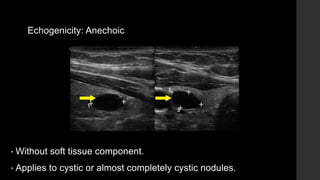

Echogenicity: Anechoic

• Without soft tissue component.

• Applies to cystic or almost completely cystic nodules.